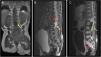

Niña de 2 años con antecedente de hoyuelo y hemangioma lumbar diagnosticado al nacimiento, no estudiado previamente. Presenta paraparesia progresiva de 2 meses de evolución, atrofia muscular en piernas, estreñimiento y tendencia a retención urinaria, acompañado de bultoma subyacente al hemangioma. Se solicita resonancia magnética (RM) que muestra gran masa intrarraquídea rodeando al cono medular y extensión presacra con áreas quísticas y realce heterogéneo del contraste (fig. 1). Analítica completa normal, alfa-fetoproteína y β-HCG negativas en sangre.

Resonancia magnética prequirúrgica. A) Corte coronal, secuencia T1, masa intrarraquídea hipointensa (flecha amarilla). B) Corte sagital, secuencia T2, masa intrarraquídea hiperintensa en cono medular (flecha amarilla). Destaca hiperintensidad en relación con gran edema en el tramo distal de la médula (flecha roja). C) Corte sagital, secuencia T1 tras la administración de gadolinio. Se observa masa intradural con captación periférica de contraste inmediatamente inferior al cono medular (flecha amarilla), y extensión de la misma a territorio presacro (flecha roja).